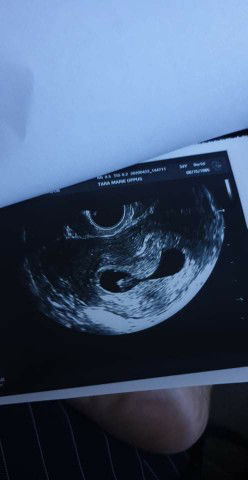

contractions at 8 weeks.

Hello momshies. I just had my first USD today. Baby's heartbeat was 170 bpm but doctor said that I had early contractions so now I am taking progesterone per vagina and aspirin per mouth. Anyone who experienced this? This is my 2nd pregnancy. I had my first miscarriage last 2017 :(